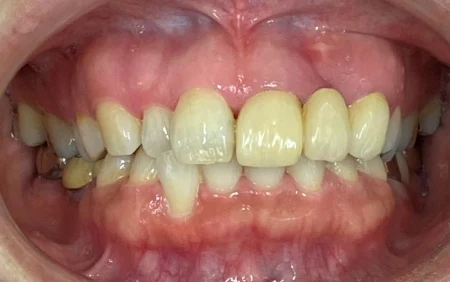

拝見すると、左上の前歯(側切歯/2番)が欠損しており、両隣の歯(中切歯/1番、犬歯/3番)を土台にして欠損部に人工歯「ポンティック」を繋げている被せ物「ブリッジ」が入っていました。

ポンティックと歯ぐきとの間に隙間があり、息が漏れるため発音障害を起こしていました。

歯ぐきとポンティックの間の隙間をなくすために、歯ぐきの形を整えた後、変色せず天然の歯が生えているようなポンティックを橋渡しする白い被せ物「オベイドポンティックセラミックブリッジ」を作り直す治療をご提案しました。

まず、今まで入っていたブリッジを除去し、歯ぐきを卵円形「オベイド」になるよう一部トリミングを行いました。

歯ぐきの形が落ち着いた後、ブリッジの土台の歯を削り直し、最終的な被せ物の型取りを行ってから、ポンティックが歯ぐきに密着するよう装着しました。